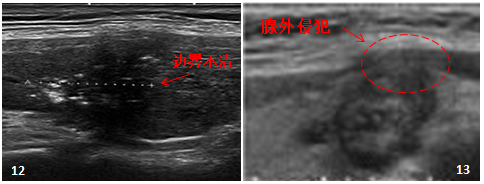

步骤 4:观察结节边界/边缘

边界是指结节与周围甲状腺组织之间的分界。

大多数良性肿瘤生长广泛,并被包膜包围,因此边界光滑。 由于其浸润性生长模式,恶性肿瘤与周围甲状腺组织的界限不清晰(图12)。 但也有例外,如良性结节性甲状腺肿,无包膜,融合生长,边界不清。 甲状腺滤泡状癌有包膜,边界清晰。

如果边界清楚的结节被包膜或血管侵犯,则更有可能是恶性肿瘤(图13)。

图 12:“ATA 结节的超声表现和恶性肿瘤风险”

图13:ETA指南“成人甲状腺结节超声恶性风险分层”